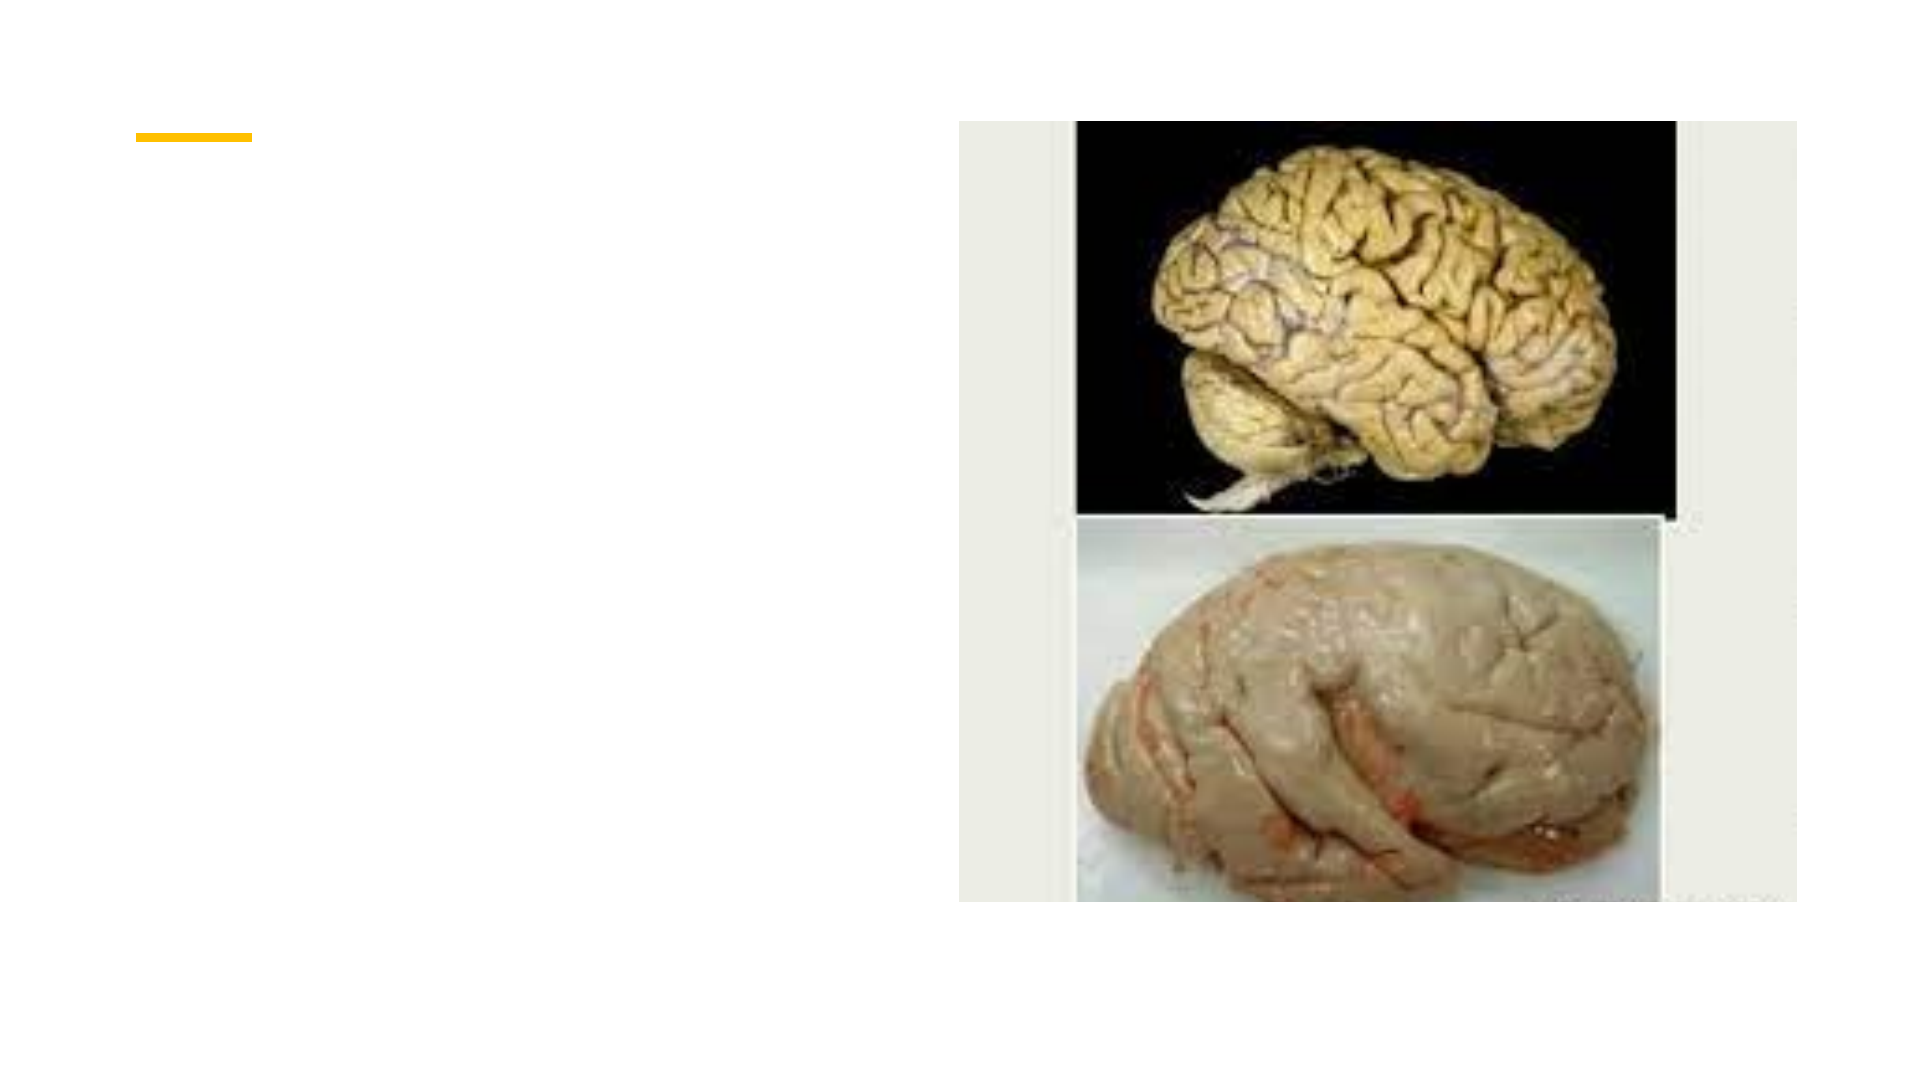

Lisencefalia Ausência de giros e sulcos Hereditário: Lhasa apso Humanos – hipóxia intrauterina Sinais clínicos • Se manifesta no primeiro ano de vida • Alteração comportamental • Déficit de aprendizado • Déficit visual e olfatório • Convulsões Diagnóstico: somente com tomografia e ressonância magnética Prognóstico: ruim Tratamento: antidepressivo